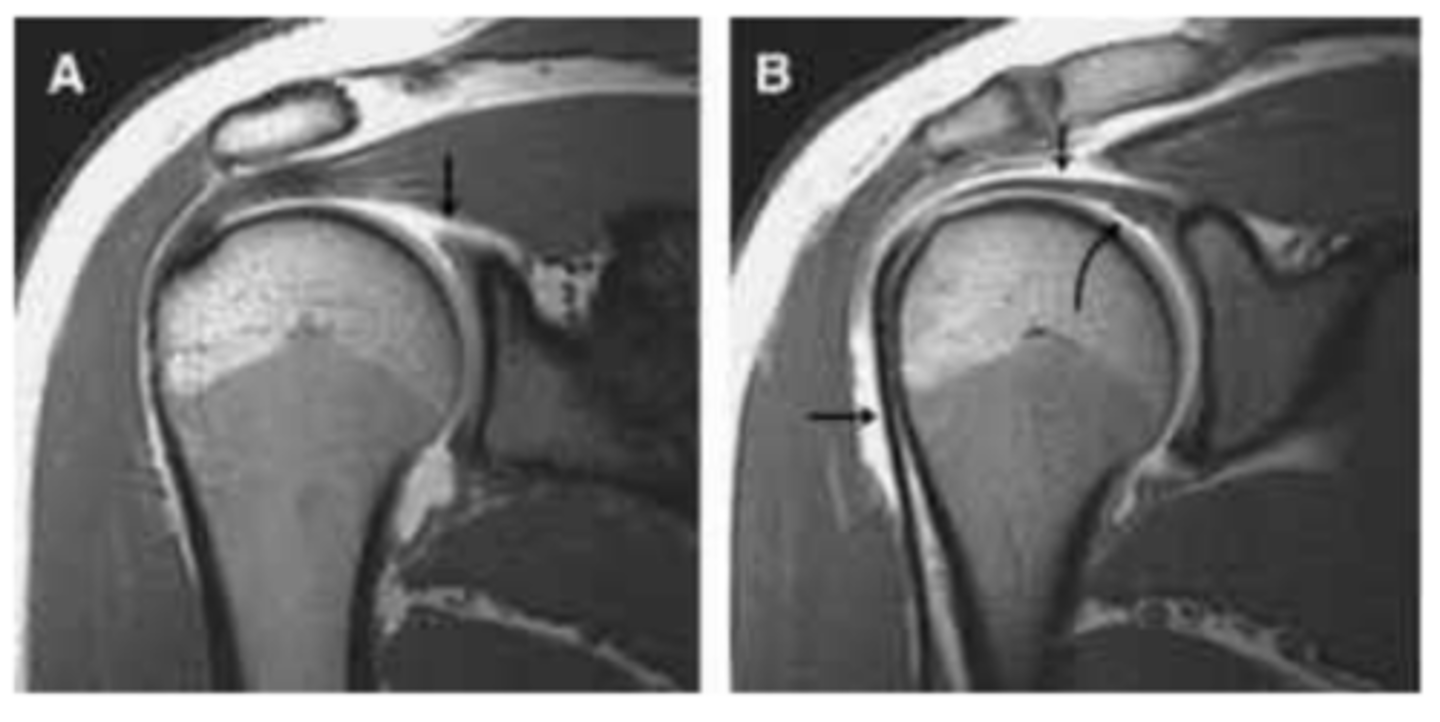

Normal superior and inferior glenoid labra without sub-labral leak of contrast material.

What does image A show?

Superior labrum (curved arrow) shows normal relationship to biceps tendon (straight arrows).

What does image B show?